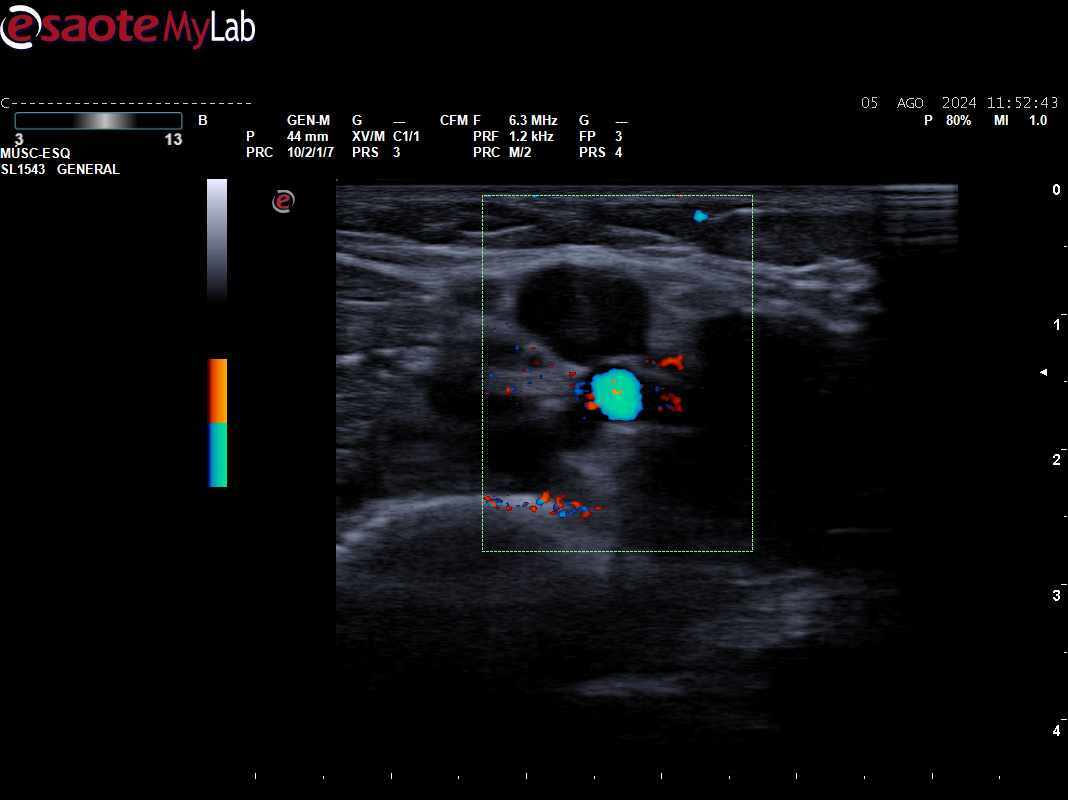

Descripción de los hallazgos ecográficos y las imágenes más relevantes para la resolución del caso

Se objetiva ausencia de compresibilidad y señal Doppler con material hiperecogénico intraluminal compatible con trombosis en territorio braquial de MSI.